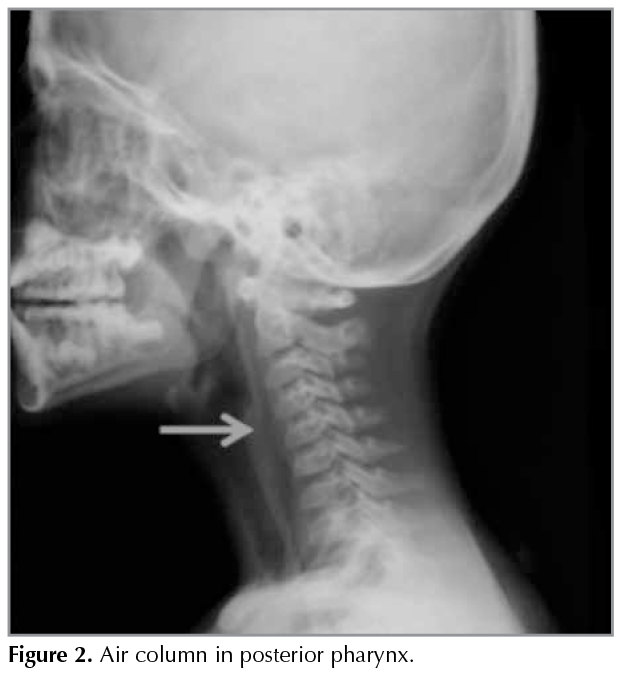

The cervical spine X-Ray showed that there was an air column in posterior pharynx (Figure 2). Chest/Neck? Computed tomography (CT); interstitial air was? present around the right inferior pulmonary vein, spread along the mediastinal? fat plans and the neck fasia which? was also evaluated as Macklin effect (Figure 3). On her laboratory investigations; White blood cell was 17.000/mm3 and CRP was 1.6 mg/dL. Other laboratory findings including electrolyte levels, blood gas analysis were within normal limits. The patient also was treated conservatively, and symptoms resolved 4 days postadmission.

Figure 2